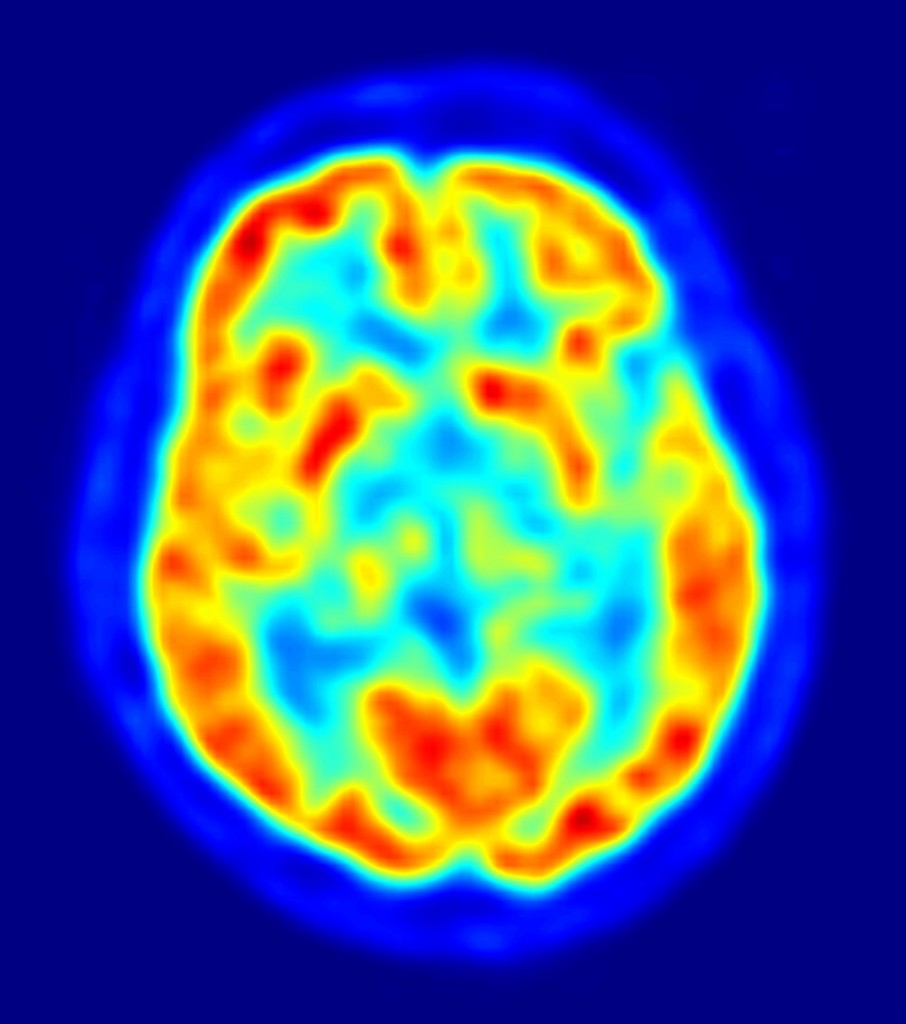

Author Yellowlees Douglas set out the 6 important points a writer should know about how our brains work before they put pen to paper/finger to keyboard.

Author Yellowlees Douglas set out the 6 important points a writer should know about how our brains work before they put pen to paper/finger to keyboard.